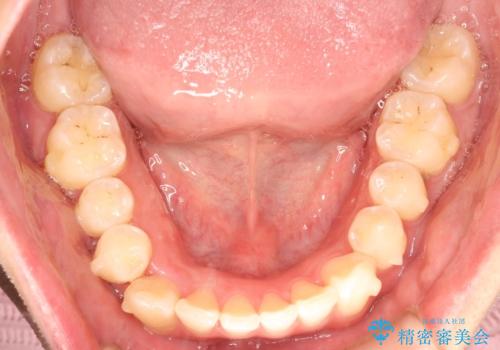

前歯がガタガタ インビザラインによる矯正

- 前歯がガタガタ、下の犬歯が飛び出ているのを主訴に来院されました。

下の奥歯を後方へ移動させてスペースを確保して、前歯を並べる計画としました。

目立たない装置をご希望されたので、インビザラインにて矯正治療を行いました。

使用時間を守っていただけたので、比較的スムーズに矯正を終了することができました。